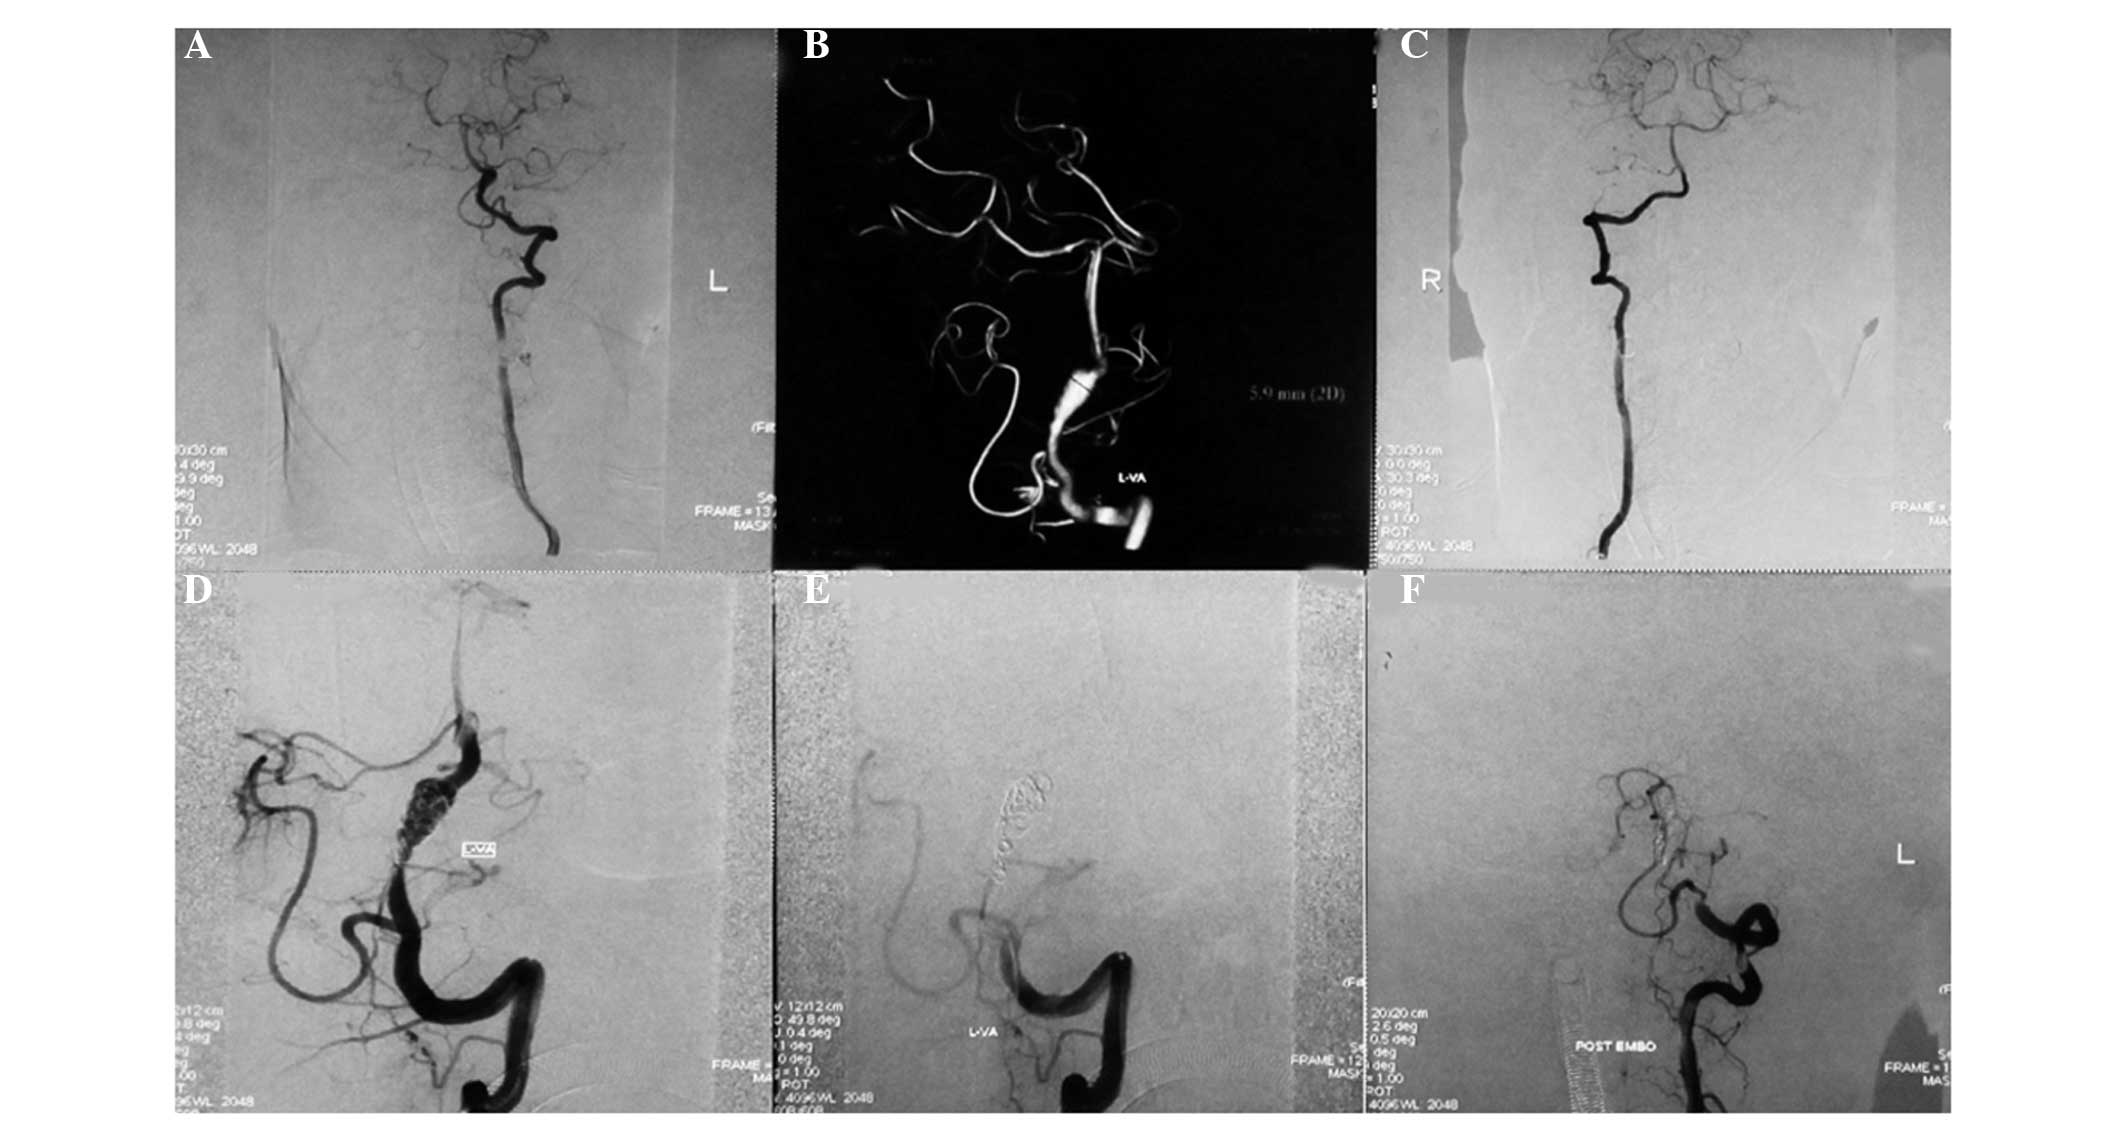

Among the 10 patients with type I aneurysms, four patients with type Ia received coiling with parent artery occlusion (Fig. 1), one patient with type Ia received stent-assisted coiling, three patients with type Ib received stent-assisted coiling (Fig. 2), one patient with type Ib received coiling only and one patient with type Ib was treated conservatively. Among the 13 patients with type II aneurysms, two patients with type IIa received coiling with parent artery occlusion (Fig. 3), five patients with type IIa received stent-assisted coiling (Fig. 4) and all six patients with type IIb received stent-assisted coiling. Among the eight patients with type III aneurysms, four patients with type IIIa received coiling with parent artery occlusion (Fig. 5), one patient with type IIIa received stent-assisted coiling (Fig. 6), two patients with type IIIb received stent-assisted coiling and one patient with type IIIb received coiling only.

Figure 2

(A) Digital subtraction angiography (DSA) and (B) 3D-DSA images showing a type Ib dissecting aneurysm of the left vertebral artery located distally to the posterior inferior cerebellar artery and the contralateral vertebral artery, exhibiting hypoplasia. DSA images showing the (C) right vertebral artery and (D) stent-assisted coiling treatment of the left vertebral dissecting aneurysm. The post-treatment angiograms show (E) complete obliteration of the aneurysm and (F) that the left vertebral artery was filled well.